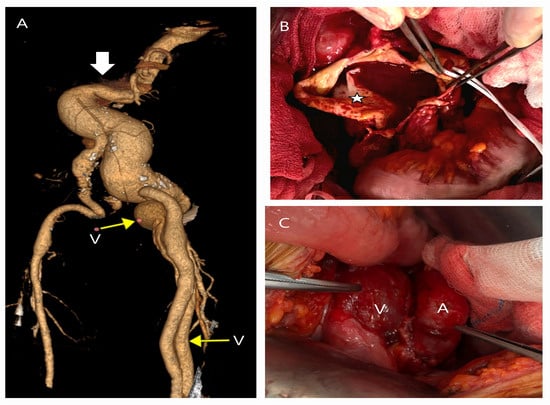

5.1. Failure of EVAR

5.2. Conversion to Open Surgery